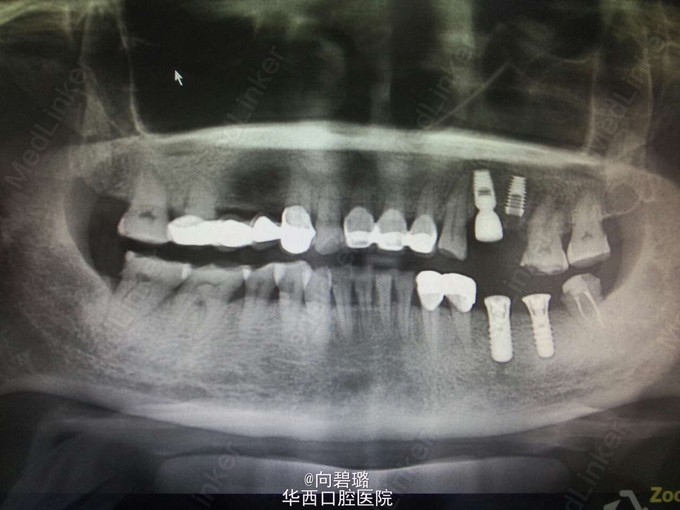

4个月后患者复诊,诉疼痛未缓解,拍片显示25牙根尖暗影变小,但未完全消除。 经患者本人考虑,在局麻下拔除24、25牙,行即刻种植手术。 随着显微超声技术和镍钛机动器械的发展,根管再治疗的成功率有了显著的提高。然而,由于根管再治疗相对于首次根管治疗病因复杂,去除根管充填物较困难,所以远期预后不佳,需要跟患者进行充分的沟通。